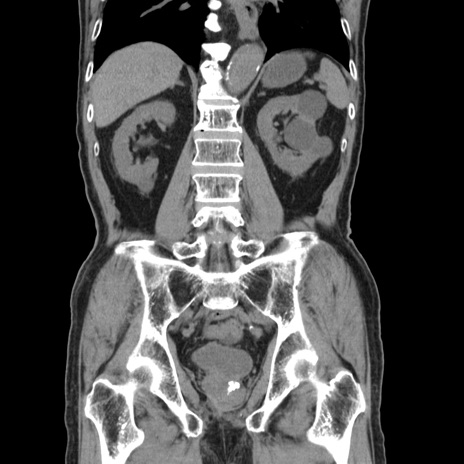

症例24(冠状断像)

【症例】80歳代男性

【既往歴】直腸癌(Mile手術)、胆摘

【身体所見】意識清明、BT 35.9℃、BP 221/93mmHg、SpO2 97%(RA) 、腹部:左ストーマ周囲に限局性の腹部膨隆あり。 膨隆部自発痛・圧痛あり・軟。